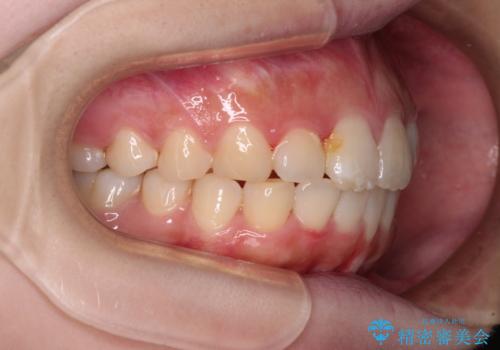

前歯のデコボコをインビザラインできれいに整える

- 前歯のデコボコと上下の隙間を気にして来院された患者様です。

前歯の捻れを改善するとともに、口元が少しでも引っ込むように治療計画を立て、仕上げることができました。